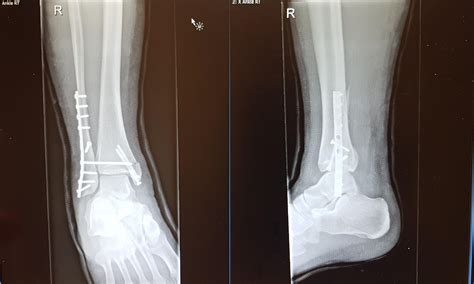

The results of your broken ankle Xray dictate your recovery plan. If the bone pieces are aligned, your doctor may suggest conservative treatment. This involves wearing a cast or specialized boot for several weeks to allow the body's natural healing process to bridge the gap in the bone.

However, if the Xray indicates that the joint surface is uneven or that the bone is severely displaced, surgery may be recommended. This is often referred to as Open Reduction Internal Fixation (ORIF), where a surgeon uses hardware like metal plates and screws to hold the bones in the correct anatomical position while they heal. Following surgery, you will likely undergo follow-up Xrays periodically to monitor bone union.